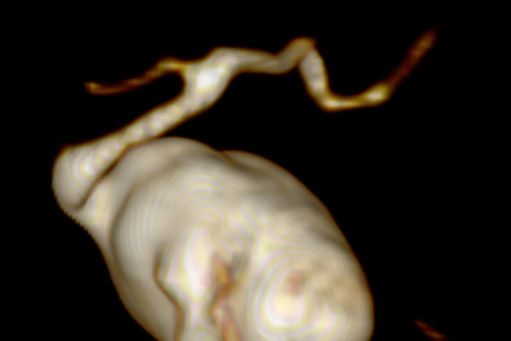

Die Magnetresonanztomographie nutzt keine Röntgenstrahlen sondern Magnetfelder und hochfrequente elektromagnetische Wellen. Das durch hochempfindliche Antennen gewonnene Signal wird in einem komplizierten Auslese- und Messverfahren umgesetzt und in ein Bild umgewandelt.

Der Vorteil der MRT ist die oft bessere Darstellbarkeit entzündlicher und tumoröser Veränderungen in sämtlichen Weichteil-Geweben, bzw. -Strukturen; Nerven- und Hirngewebe werden z.T. erst durch die MRT-Untersuchung hinreichend beurteilbar. Oft wird Kontrastmittel zusätzlich benötigt, um Entzündungsherde oder auch Tumorgewebe noch besser darzustellen.

• Gefäße